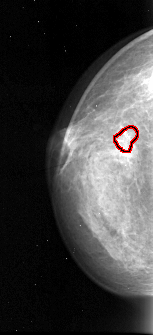

A_1096_1.LEFT_CC

LEFT_CC LINES 4021 PIXELS_PER_LINE 1831 BITS_PER_PIXEL 16 RESOLUTION 42 OVERLAY

FILE: A_1096_1.LEFT_CC.OVERLAY

TOTAL_ABNORMALITIES 1

ABNORMALITY 1

LESION_TYPE CALCIFICATION TYPE PLEOMORPHIC DISTRIBUTION CLUSTERED

ASSESSMENT 4

SUBTLETY 5

PATHOLOGY MALIGNANT

TOTAL_OUTLINES 1

BOUNDARY